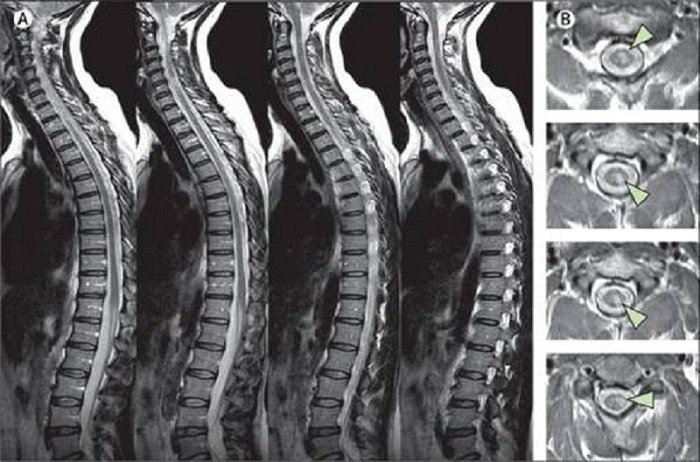

Hiện tại, MRI là xét nghiệm hình ảnh nhạy cảm nhất có sẵn cho các vấn đề tại cột sống nói chung và cột sống thắt lưng cùng nói riêng. Nguyên nhân là vì cấu trúc giải phẫu tại khu vực này tương đối phức tạp, bao gồm nhiều thành phần khác nhau, mật độ khác nhau như xương, đĩa đệm, dây chằng, thần kinh và mô mềm xung quanh mà trên ảnh MRI có thể phân biệt được tốt hơn.

Hình ảnh MRI của cột sống rõ ràng và chi tiết hơn so với hình ảnh thu được bằng các phương pháp hình ảnh khác, nhất là các bệnh lý trên tủy sống và dây thần kinh khi các bất thường có thể bị che khuất bởi xương trong các phương pháp chẩn đoán hình ảnh khác.